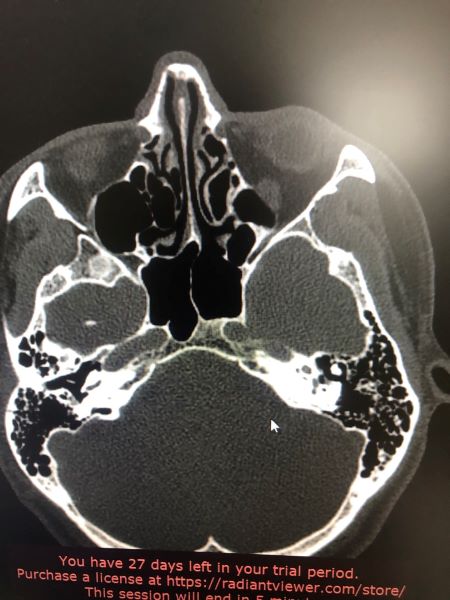

Киста основной пазухи

Пациент обратился в клинику №1 ВиТерра Беляево к ЛОР-врачу Богдановой Е.С. с жалобами на выраженную головную боль в течение 2-х лет! Неоднократно обследован и проходил лечение в других клиниках. Без эффекта.

Пациент после осмотра был направлен доктором Богдановой Е.С. на КТ придаточных пазух носа в клинике ВиТерра. По результатам обследования обнаружена киста основной пазухи слева. Пациент направлен в стационар для хирургического лечения.

Через 2 месяца пациент пришёл на контрольный осмотр.

Жалоб не предъявляет. Головные боли купировались сразу же после операции.